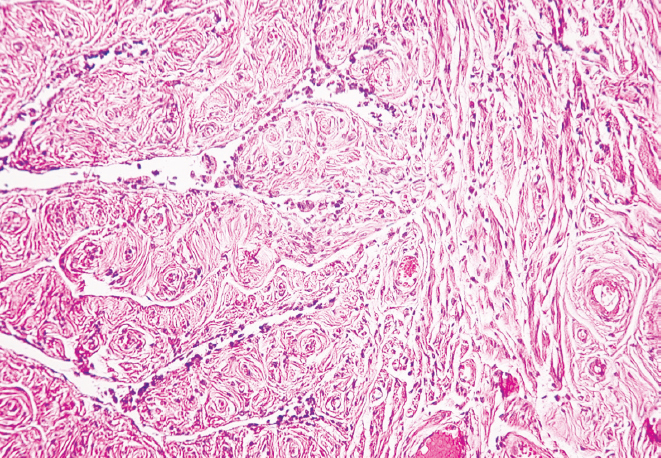

RESULTS: There was a decrease in the external diameter of the isthmus and funnel of both fallopian tubes in women from young age to old age (p < 0.01). At old age, there was a predominance of external diameter parameters of the isthmus and funnel of the right fallopian tube in comparison with those of the left fallopian tube (p < 0.01), while at young age there was only a tendency for the diameter of the isthmus and funnel of the right fallopian tube to predominate (p > 0.05). The histological study showed the presence of thickened folds of the mucous membrane and flattened epithelium in the studied areas in older women, thinning of the muscular membrane layers and overgrowth of connective tissue in comparison with the samples taken for the study in younger women.

CONCLUSIONS: Morphologic restructuring of the isthmus and funnel of the fallopian tubes from young to old age consists in thickening of the mucous membrane folds, flattening of the epithelium, overgrowth of connective tissue in the wall and reduction of their outer diameter with predominant parameters in the right fallopian tube.